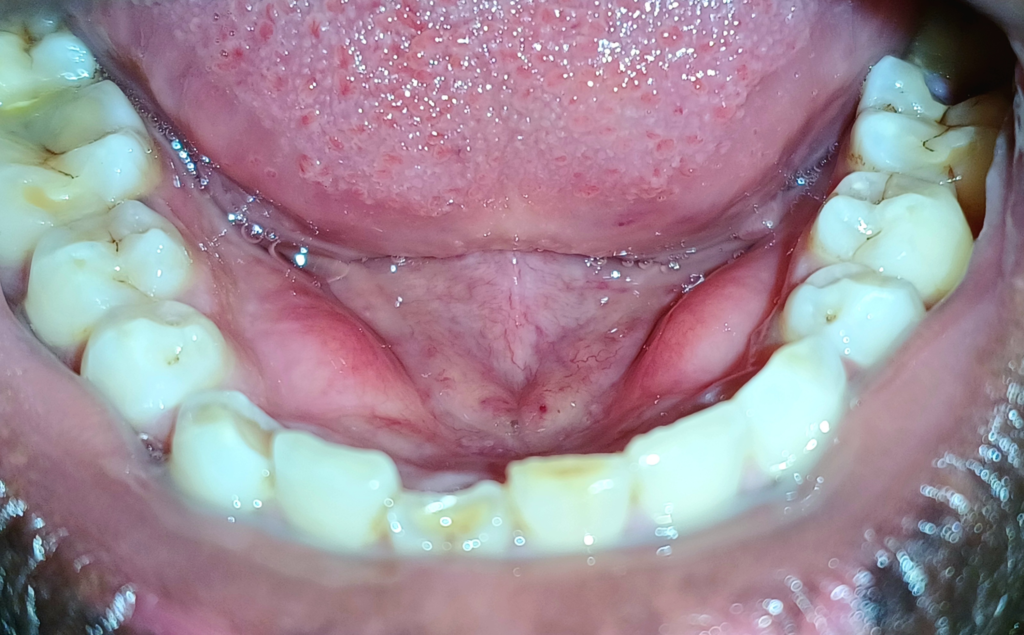

下顎骨隆起(torus mandibularis)は、下顎骨体部舌側、特に小臼歯部付近に生じる限局性の骨性隆起であり、多くは両側対称性にみられる良性の外骨症です。通常は無症候性で治療を要しませんが、義歯装着や粘膜外傷の原因となることがあります。発生学的に下顎骨は第一咽頭弓由来で、神経堤細胞から分化した間葉が膜内骨化によって形成されます。この膜内骨化骨は皮質骨優位で、機械的刺激への応答性が高いという特性をもちます。骨形成の分子基盤には、BMP–Runx2–Osterix軸が存在し、BMPがRunx2を活性化して骨芽細胞分化を誘導します。FGFシグナルは前駆細胞の増殖と分化バランスを調整します。

下顎骨隆起(torus mandibularis)と食いしばりや歯ぎしり(ブラキシズム)との関連が示されています。ブラキシズムでは咬合力が持続的・反復的に増大し、咬合応力が下顎体皮質骨へ直接伝達されます。とくに小臼歯部舌側は応力集中部位であり、骨膜や皮質骨表層に機械刺激が加わります。この刺激はメカノトランスダクション機構を介してBMP発現やRunx2活性を局所的に上昇させ、骨芽細胞活性を亢進させます。その結果、緩徐な骨付加が生じ、外骨症として顕在化します。

下顎骨隆起は、発生期に確立された膜内骨化の分子プログラムが、成人後も咬合機能負荷に応答して再活性化された結果と理解できます。腫瘍性増殖ではなく、力学的適応に基づく制御された骨形成亢進です。顎顔面骨が神経堤由来で高い可塑性をもつこと、そしてブラキシズムがその可塑性を形態変化として可視化することを示す代表的現象と考えられます。